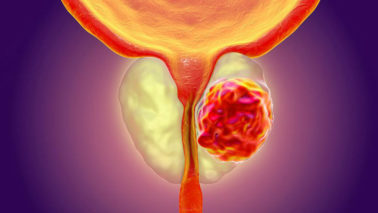

Sexual impotence could cause problems with interpersonal associations, in addition to lower a singleÂ’s self impression and self-self confidence. Very often, sexual impotence provides rise to extreme despair and psychological trauma, While in others, psychological aspects could be the reason for impotence. The main detail to do is tackle the condition at the earliest. If this is finished, in several situations, there may well not even be a need for any kind of clinical intervention.

Thankfully, treatment options are offered for ED. They can be generally Risk-free and successful in about 70% of situations.